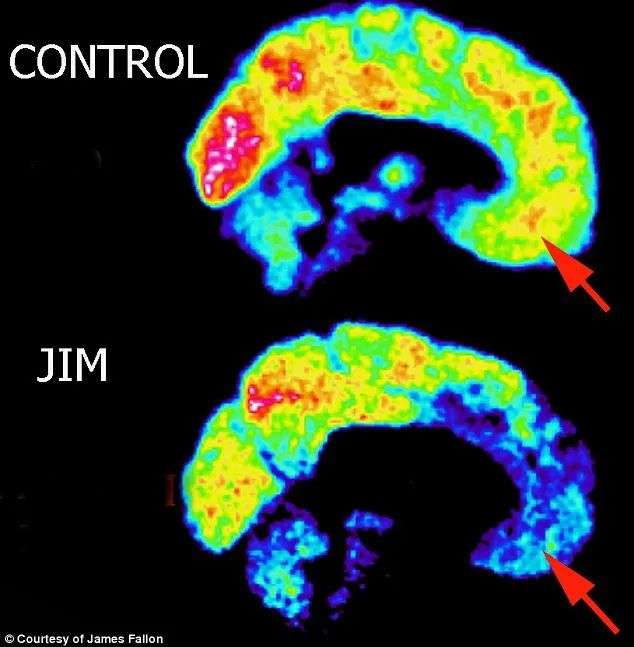

与正常成年人相比,精神病患者的 PET 扫描显示社交和情感中心的大脑活动减少。

图片提供自JAMES FALLON

与健康的大脑相比,杀手的大脑在眶皮层和杏仁核周围的活动要少得多——这些区域可以防止冲动行为并控制社会行为、抑制、道德和伦理。

而他的脑部扫描,确实明明白白显示着同样的杀手模式。他的大脑在眼睛后面那个关键的眶皮层区域有黑色的低活动斑块。

“大脑该区域活动低下的人是随心所欲的人或反社会者,”他说。